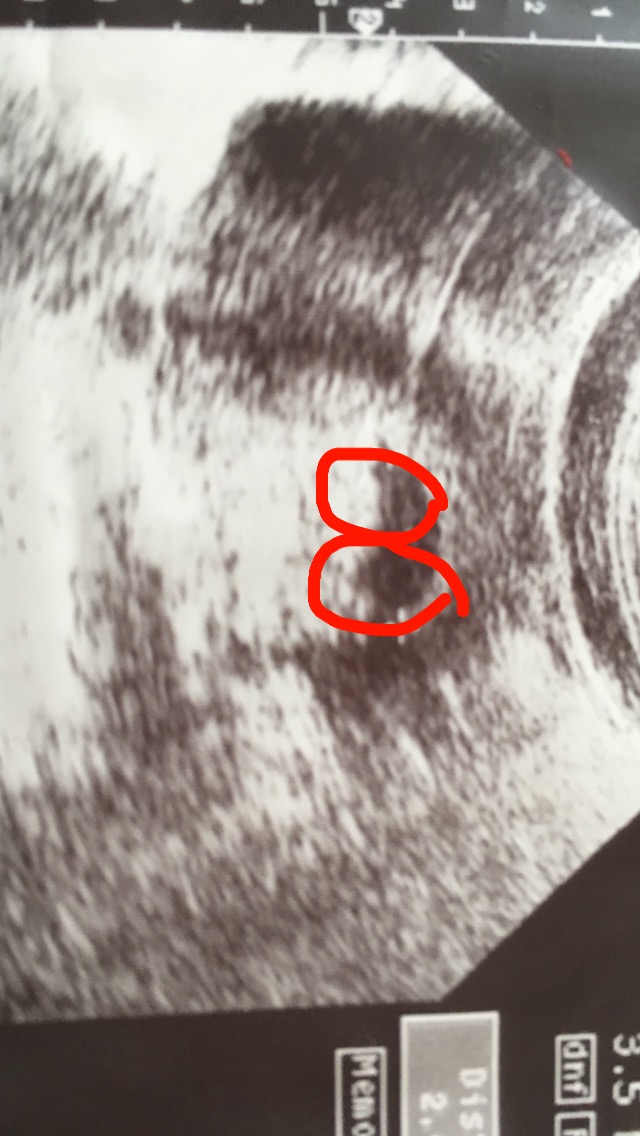

5 6 ssw ultraschall zwillinge Sie sind 5 Wochen schwanger (SSW 5) oder in der 6 Schwangerschaftswoche Zwillinge in SSW 5 Sicherlich haben Sie jetzt das Bedürfnis, all Ihren Freundinnen und Freunden vom kleinen Geheimnis zu erzählen, das da in Ihrem Bauch wächst Vielleicht aber wollen Sie ganz einfach nur mit jemandem reden, über das. Der im Ultraschall gerade erkennbare (sekundäre) Dottersack besteht aus den 3 Schichten Ektoderm, Mesoderm, Endoderm, wobei in der mesodermalen Schicht wichtige Vorgänge der Erythropoese stattfinden Der Prozess der Regression des Dottersacks beginnt ab der 10 SSW, nach der 12 SSW ist der Dottersack nur noch selten erkennbar. 6 SSW Ultraschall Das ist zu sehen Die Schwangerschaft in der 6 Woche ist ein aufregender Zeitpunkt für Sie, denn Ihr Baby ist jetzt eindeutig zu sehen Der Embryo ist in der 6 SSW ein etwa zwei bis vier Millimeter langes, gekrümmtes Würmchen, bei dem sich schon die Arm und Beinanlagen erahnen lassen.

Ich war in der 7 SSW zum US Zu sehen war eine Fruchthöhle mit Embryo 6 mm und Herzaktion, daneben noch eine Fruchthöhle mit einem weißen Ring darin Für mich sah das aus wie eine Fruchthöhle Anfang 6 SSW, denn da hatte ich meine Tochter Amelie das erste Mal per US gesehen. 5 und 6 SSW Plazenta & Fruchtblase Jeder Zwilling hat seine eigene Plazenta und Fruchtblase Das Herz beginnt ab der sechsten Schwangerschaftswoche zu schlagen Im Ultraschall kann man anhand der zwei Herzen erkennen, dass es sich um Geschwister handelt 8 SSW Arme, Beine & Nervensystem In der 8. Von der 6Schwangerschaftswoche (SSW 6) spricht man auch als SSW 50 bis 56 54 bedeutet zum Beispiel, dass 5 Wochen und 4 e seit dem ersten Deiner letzten Periode vergangen sind Dein Embryo im Bauch existiert nun seit etwa 3 Wochen.

Ihre Zwillinge in der 6 Woche (SSW5) Alter 3 Wochen Grösse 153 mm so gross wie ein Sesamkorn Sie sind 5 Wochen schwanger (SSW 5) oder in der 6 Schwangerschaftswoche Zwillinge in SSW 5 Sicherlich haben Sie jetzt das Bedürfnis, all Ihren Freundinnen und Freunden vom kleinen Geheimnis zu erzählen, das da in Ihrem Bauch wächst. 5 6 ssw ultraschall zwillinge Sie sind 5 Wochen schwanger (SSW 5) oder in der 6 Schwangerschaftswoche Zwillinge in SSW 5 Sicherlich haben Sie jetzt das Bedürfnis, all Ihren Freundinnen und Freunden vom kleinen Geheimnis zu erzählen, das da in Ihrem Bauch wächst 7 SSW, kein Baby und Herzschlag zu sehen Alle Antworten. Etwa zwei Drittel aller Zwillinge sind zweieiig Wenn im Ultraschall nur eine Embryonalhülle (äussere Eihaut) nachweisbar ist, handelt es sich um eineiige Zwillinge Dieses sichere Zeichen der Eineiigkeit lässt sich am besten im ersten SchwangerschaftsTrimenon beurteilen Nach der 16 SSW ist das vollständige Antwort lesen.